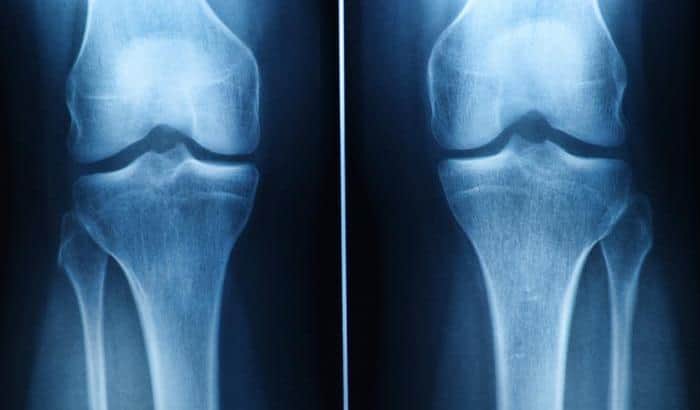

Understanding Cartilage and Its Damage

Cartilage is crucial for joint function, providing cushioning and flexibility. Damage, whether from trauma or conditions like osteoarthritis, reduces its effectiveness.